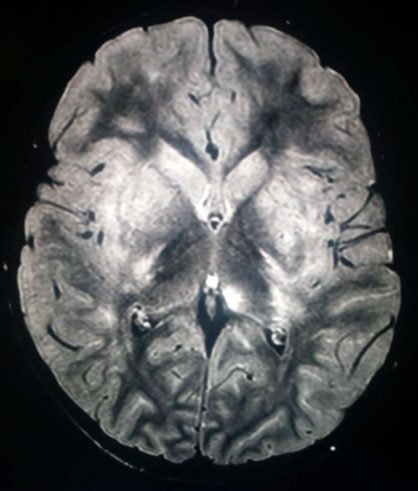

di Emergenza e Accettazione, dove viene riscontrata una leucocitosi neutrofila (26.440/mm3, neutrofili 88,9%) e una adenomesenterite all’ecografia, per cui dopo breve osservazione viene dimessa. Dopo un mese alla sintomatologia si aggiunge febbre (38,5 °C), deviazione del collo, astenia agli arti inferiori e deambulazione incerta, per cui si ricovera. È sofferente, irritabile e presenta rigidità nucale con posizione preferenziale supina. Nel sospetto di meningoencefalite viene eseguita una RMN cranio-encefalo-rachide, che mostra un’alterazione di segnale a carattere flogistico/edemigeno corticale e sottocorticale in sede parietale, caudale occipitale e temporale omolaterale con enhancement leptomeningeo e analoga alterazione dei talami (Figure 1 e 2).